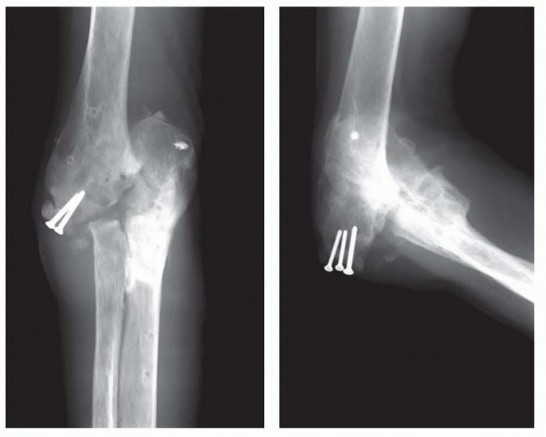

15 MIN READ Surgical Management of Traumatic Conditions of the Elbow: Interposition Arthroplasty يناير 2023 Read More